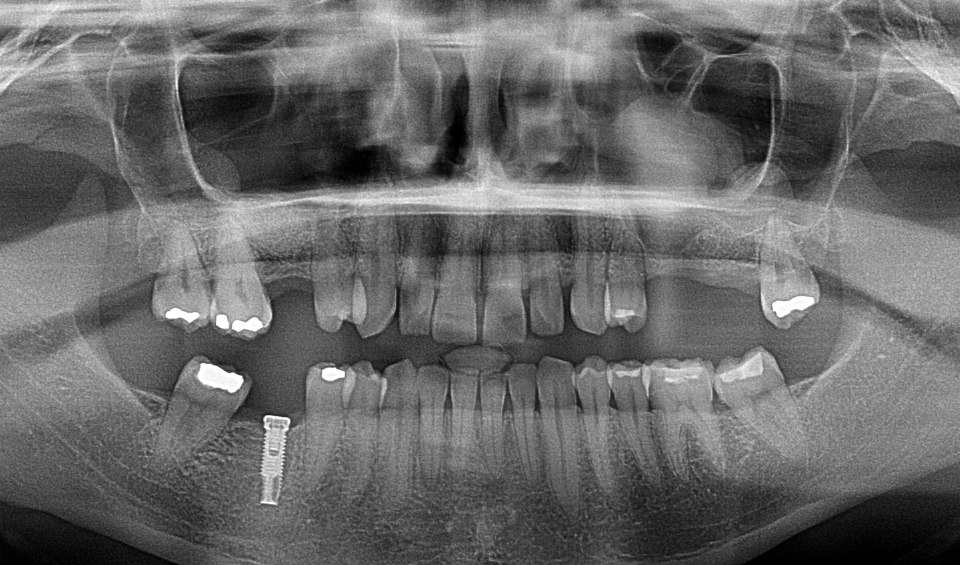

Ortopantomografia digital amb implant dental realitzada a la Clínica Dental Ariadna Barrachina d'Arenys de Munt

ORTOPANTOMÒGRAF

A més, comptem amb un ortopantomògraf, una eina essencial per obtenir radiografies panoràmiques de la mandíbula i les dents. Gràcies a aquest equipament, podem realitzar ortopantomografies amb alta precisió, la qual cosa ens ajuda a detectar problemes que podrien passar desapercebuts amb altres mètodes.